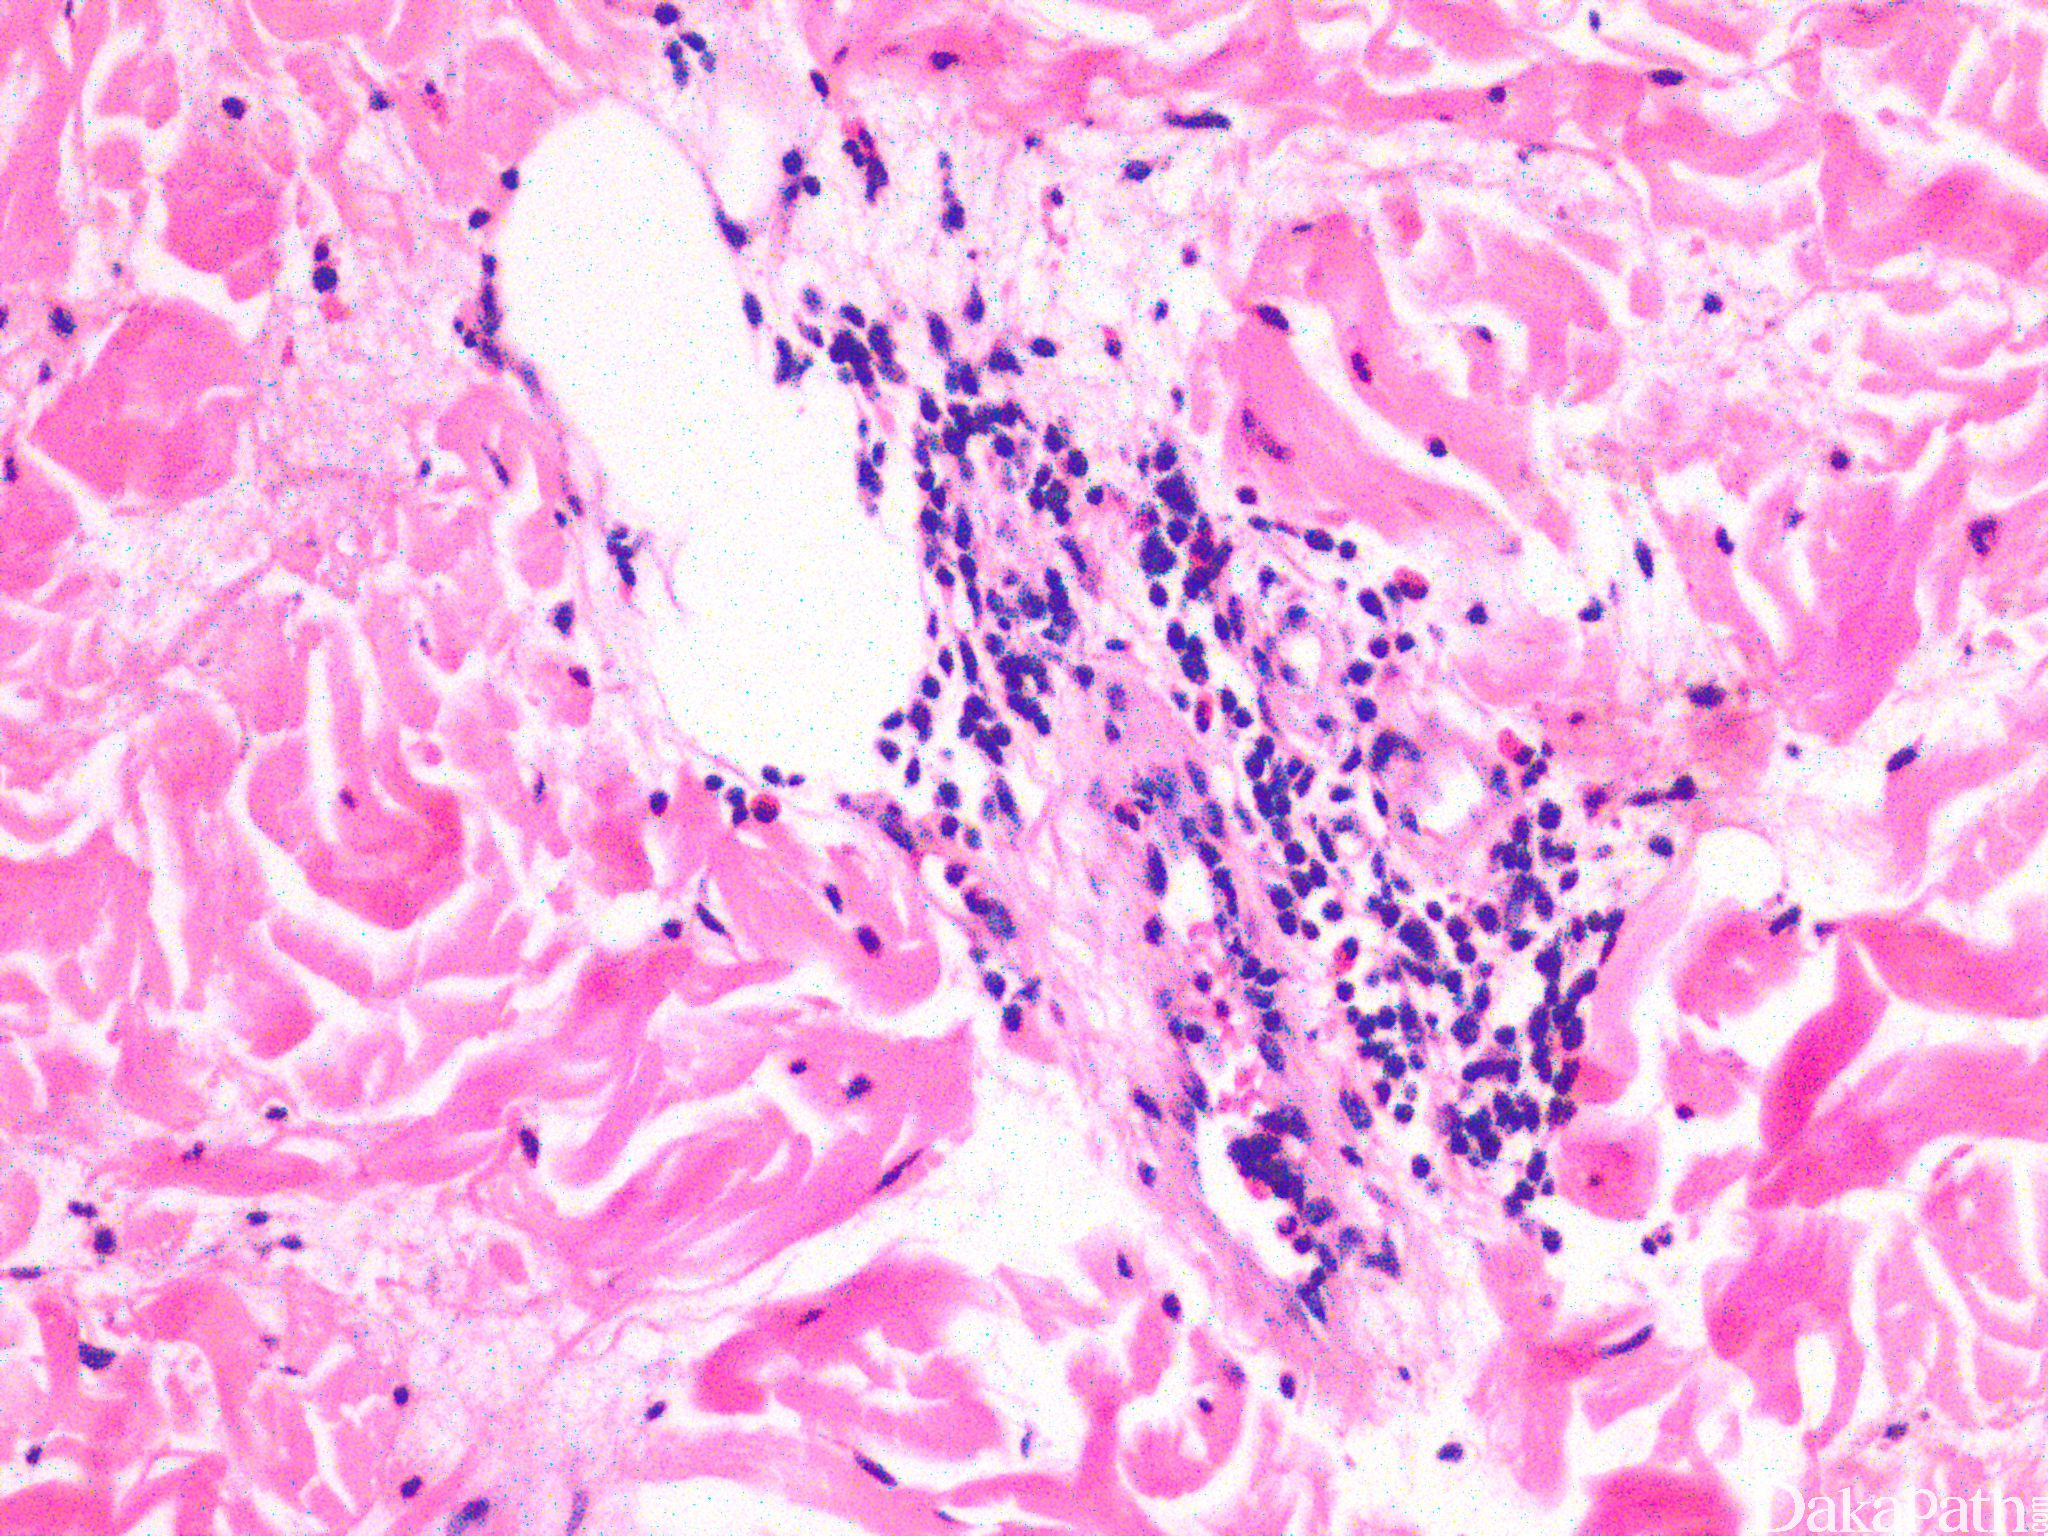

Dermalhypersensitivityreaction